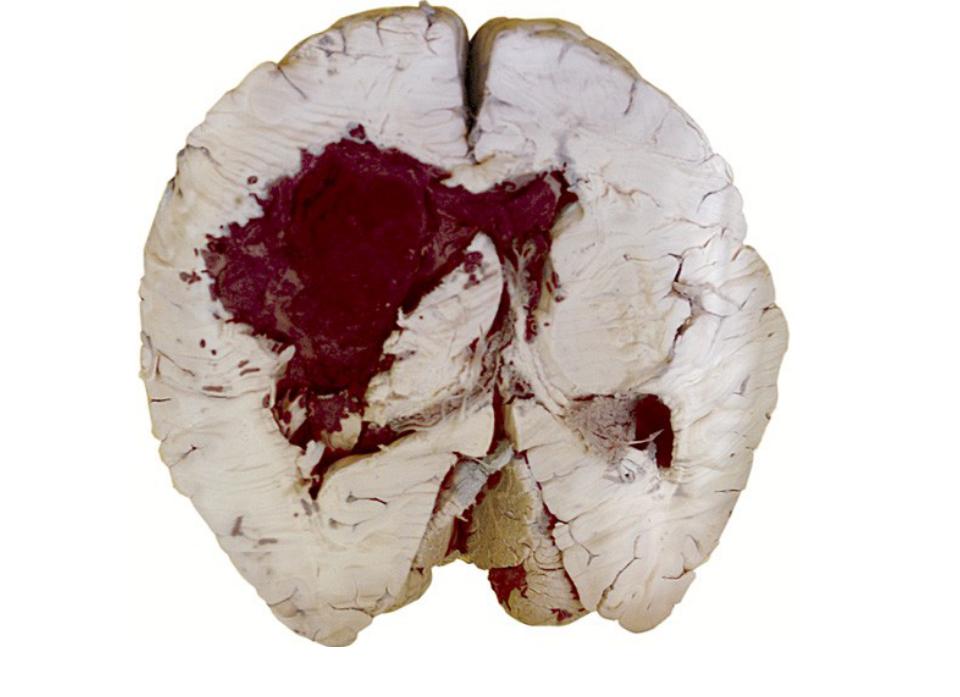

Кровоизлияние в мозг как причина разных зрачков

Травмы головы, возникающие в результате воздействия внешних сил, таких как падения или удары, могут привести к неравномерному диаметру зрачков. Это связано с образованием кровоизлияний в мозге, которые затрудняют выявление внешних признаков. Избыточное количество крови, проникающее в мозговую ткань, вызывает сжатие ее структур.

Если на одной стороне сжимаются нервы, отвечающие за изменение размера зрачка, а на противоположной стороне кровотечение не приводит к сжатию, это может стать причиной различия в диаметре зрачков.

Серьезные симптомы, указывающие на опасное для жизни кровоизлияние в мозг, включают помутнение сознания, потерю сознания и судороги.